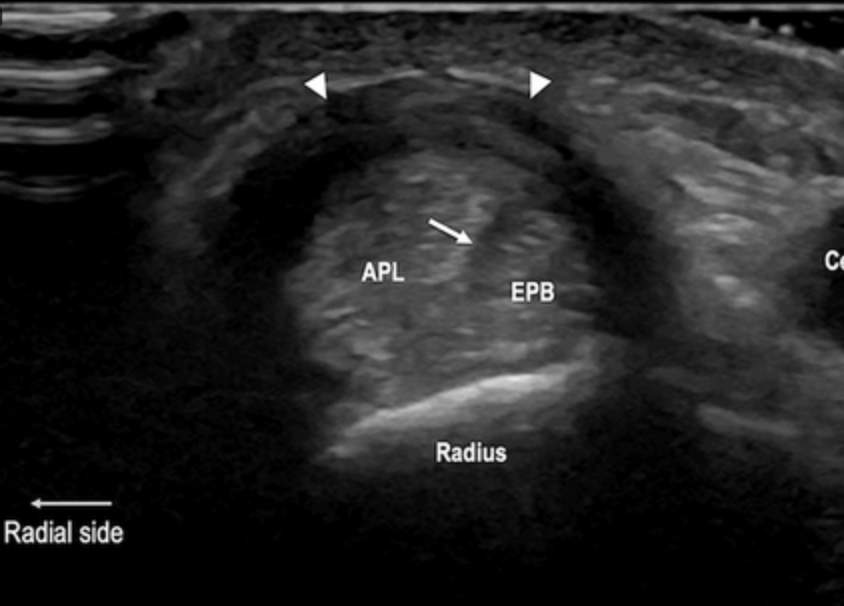

US tenosinovitis de Quervain

Engrosamiento de tendones y retinaculo

Liquido en su vaina